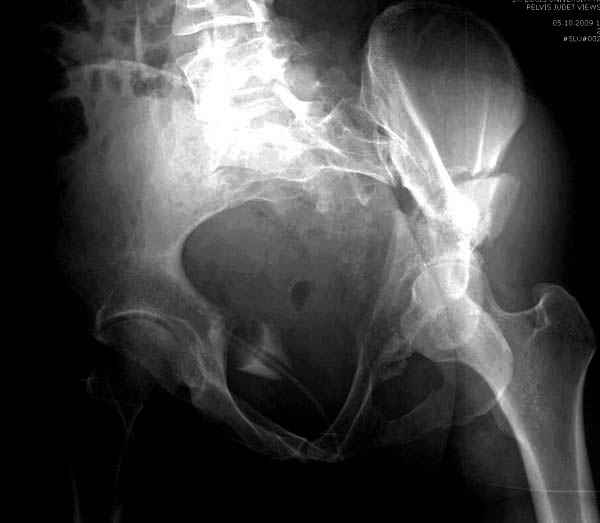

Интересно было бы посмотреть рентгенограммы до операции. У меня впечатление, что я не все вижу, что тут есть... Уважаемые Господа "тазисты" и "тазологи", к какому типу переломов вертлужной впадины по Летурнелю вы бы отнесли это случай?

Из переломов проходящих через крыло и/или заднюю стенку ни простой перелом "передней колонны" (явно имеется пером задней стенки, и не видно перелома седалищной или лонной), ни простой "поперечный", ни ассоциированный "Т-образный" (т.к есть перелом крыла и не видно перелома седалишной), ни ассоциированный "задняя колонна+задняя стенка", на ассоциированный "поперечный+задняя стенка", ни ассоциированный "передняя колонна+задняя гемисфера" (не видно перелома седалищной), ни ассоциированный "обе колонны" (не видно перелома лонной седалищной) не подходят под эту классификацию....

>Вопрос к знатокам: Так что это?

к таковым себя не причисляю, но...обычное дело для нашей страны - выкладывать 3D и не показывать стандартные проекции Judet. Дигност представляет те ракурсы, которые по-его мнению наиболее информативны, более того комп сам достраивает какие-то мелкие повреждения по 3D по своему усмотрению. По данной реконструкции можно предполагать высокий двухколонный перелом с оскольчатыми передней и задней колоннами, оскольчатую высокую переднюю колонну с задним полупоперечником или одно из перечисленных с вовлечение КПС. У меня впечатление за второй вариант, но нужно обследовать нормально - проекции, сканы.

высылаю дополнительно сканы.

Судя по представленным реконструкциям (не очень хорошего качества - много наводок)

мы имеем дело с полупоперечным переломом у которого отломался задний край или его отломали, превратив перелом в полный двухколонный.

По отдельным срезам и тем более по реконструкции трудно судить о сращении крыла и задней колонны с осевым скелетом.

Все выступающие коллеги высказались насчет необходимости стандартных снимков по Judet, потому что для определения тактики лечения переломов вертлужной впадины 3Д снимки малоинформативны.

Летурнель разработал классификсацию на основании прямого, запирательного и подвздошного рентген снимков, котоые, кроме описания характера переломов, также подсказывают адекватный доступ для репозиции перелома.

Из того минимума, что представлено, мне кажется, мы имеем дело с двухколонным переломом вертлужной впадины. Обычно медиальный (центральный) "вывих" головки встречаются в сложных двухколонных переломах со смещением.